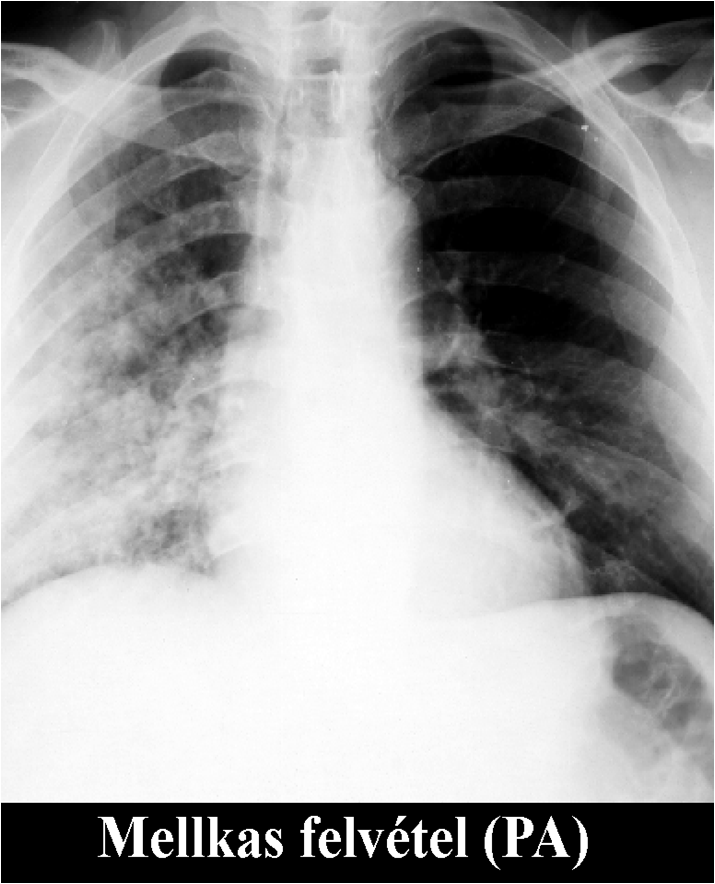

The brightness of the picture can also be altered, making too dark or too light parts of the picture assessable. The windowing allows changing of the brightness and contrast at the same time. If we change them accordingly tissues with different absorption can be highlighted. For example, low brightness and low contrast settings allows good visualization of the bone structures, but other tissues appear moderately pale. High brightness and contrast settings results in a good visualization of the lung tissue while other tissues appear bright and pale.

Figure 3.: The same CT image with soft tissue window (a) and lung window (b)